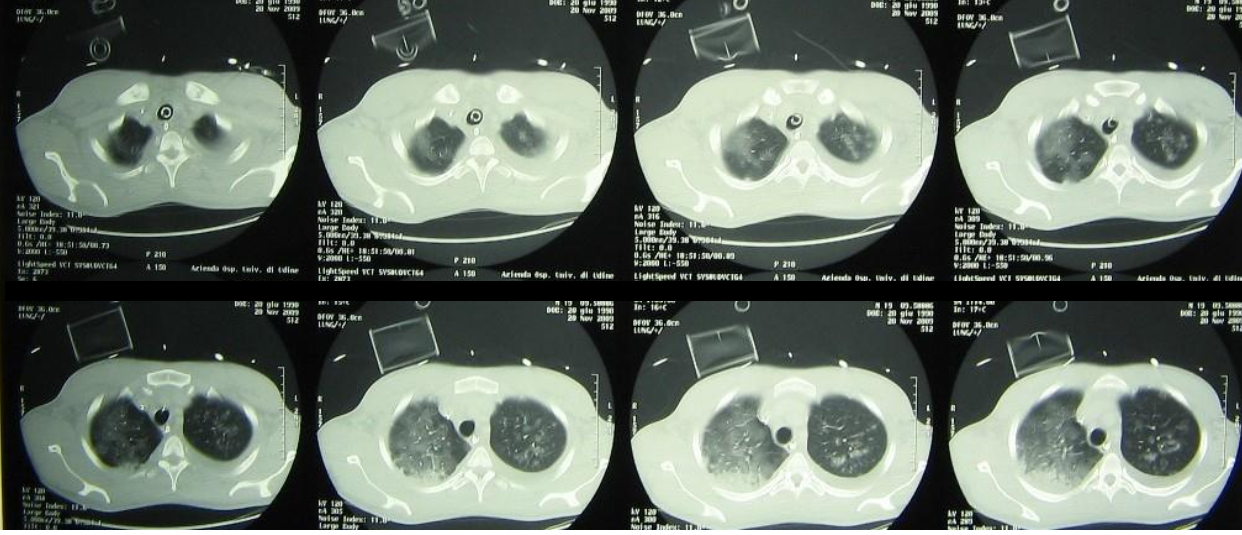

Chest imaging now shows near-complete bilateral opacification of the lungs. Echocardiography reveals global hypokinesia, more pronounced in the right ventricle, without evidence of endocarditis.

Chest CT during ICU stay showing diffuse bilateral ground-glass opacities and consolidations consistent with severe ARDS.